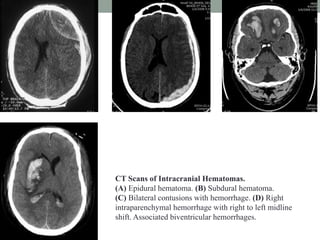

CT Scans of Intracranial Hematomas.

(A) Epidural hematoma. (B) Subdural hematoma.

(C) Bilateral contusions with hemorrhage. (D) Right

intraparenchymal hemorrhage with right to left midline

shift. Associated biventricular hemorrhages.